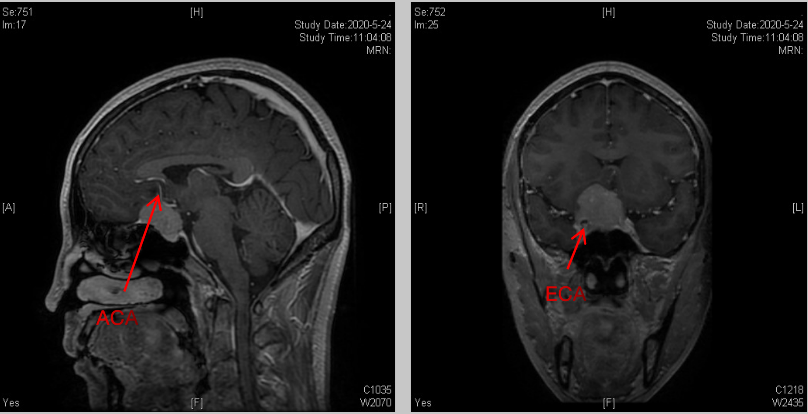

术后MRI所见:

术后复查核磁,肿瘤全切;患者恢复良好,头晕症状明显缓解,四肢活动良好。